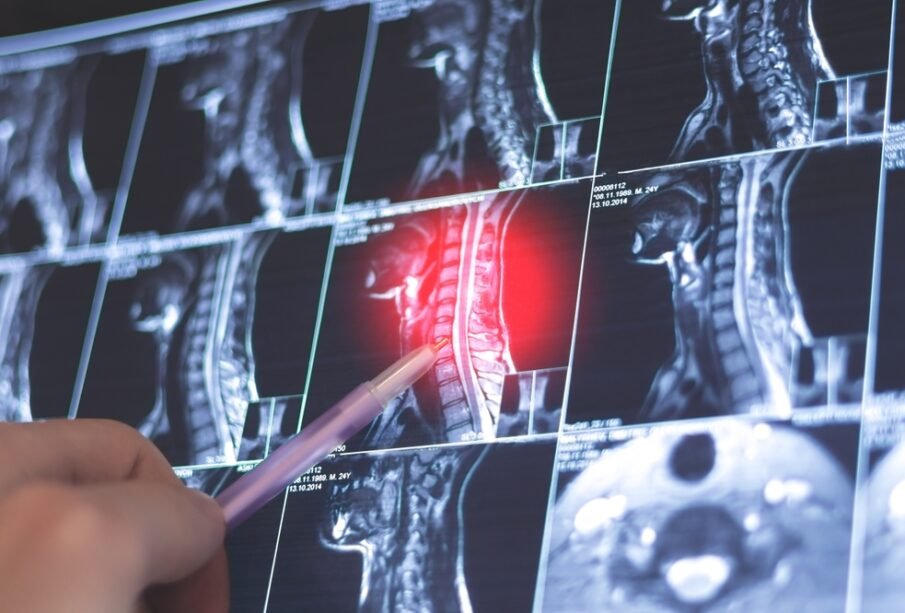

- Attēldiagnostika: rentgenogrāfija, datortomogrāfija un magnētiskās rezonanses izmeklējums palīdz novērtēt mugurkaula un locītavu bojājumu pazīmes. Magnētiskā rezonanse ļauj konstatēt iekaisuma izmaiņas vēl pirms tās kļūst redzamas rentgenogrammās.